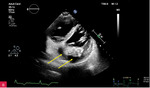

Rycina 2A, B. Zmiana u podstawy tylnego płatka mitralnego, obejmująca jego nasadę, a także fragment mięśnia ściany dolno-bocznej lewej komory w projekcji przymostkowej w osi długiej LAX (A) oraz w projekcji zmodyfikowanej, w której lepiej uwidoczniono hiperechogeniczną uwapnioną otoczkę zmiany oraz powodowany przez nią cień akustyczny (B)